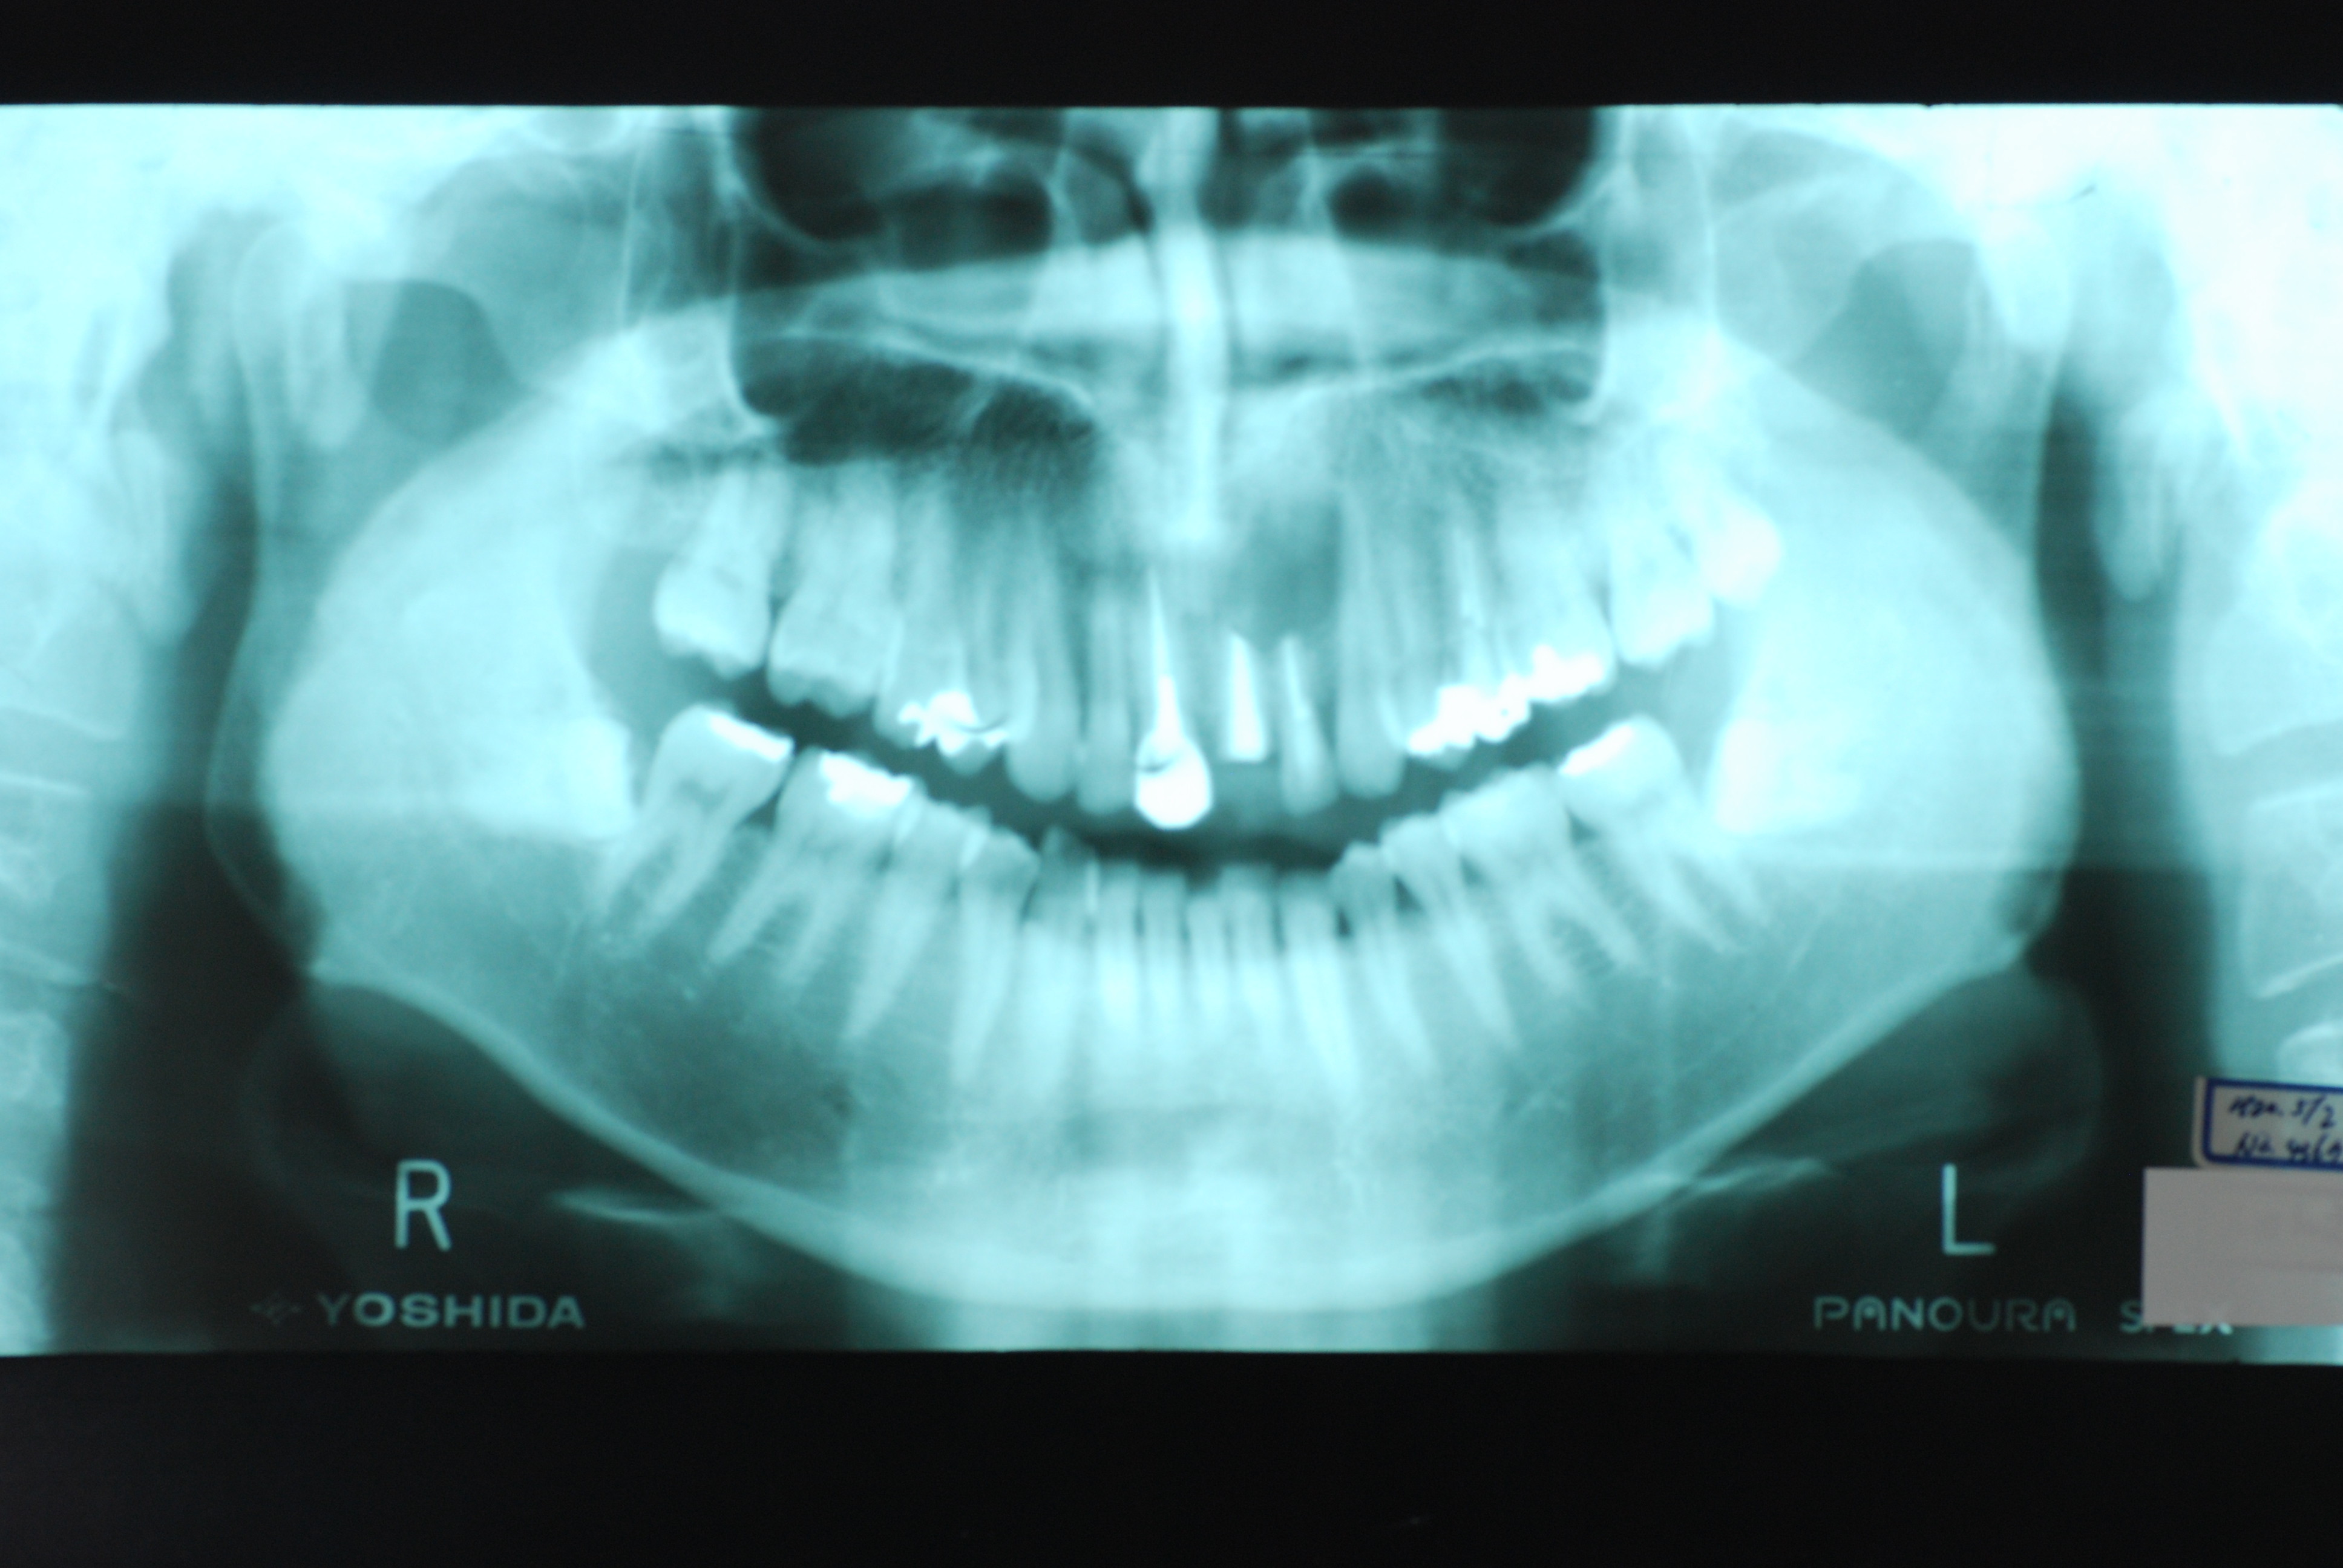

現実を見ればお口の中には“異物”である金歯、銀歯、セラミック、インプラントのオンパレードです。

必ずばい菌が侵入しないようにしてばい菌である虫歯を除去します。

銀歯の下はばい菌だらけです。こういうのはよくあります。取り残しですね。![treatment_05[1]](https://livedoor.blogimg.jp/netdental/imgs/3/a/3ad019d0-s.jpg)